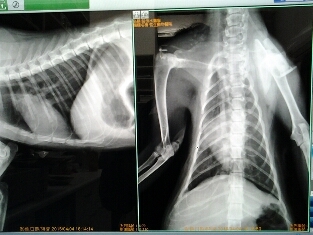

虛弱到無法站立。住院當天拍攝X光片,發現無明顯脊椎或四肢骨折,但前腳無法站立行走,從神經症狀研判是腦膜炎引起的。同時X光片明顯肺部嚴重發炎現象,呼吸道充滿鼻膿,是嚴重的肺炎。